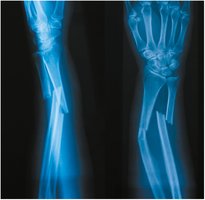

Types of Bone Fractures

Fractures are breaks in bone integrity, classified by their pattern and severity.

Type of Fracture | Description |

|---|---|

Colles Fracture | Distal radius fracture, often from a fall |